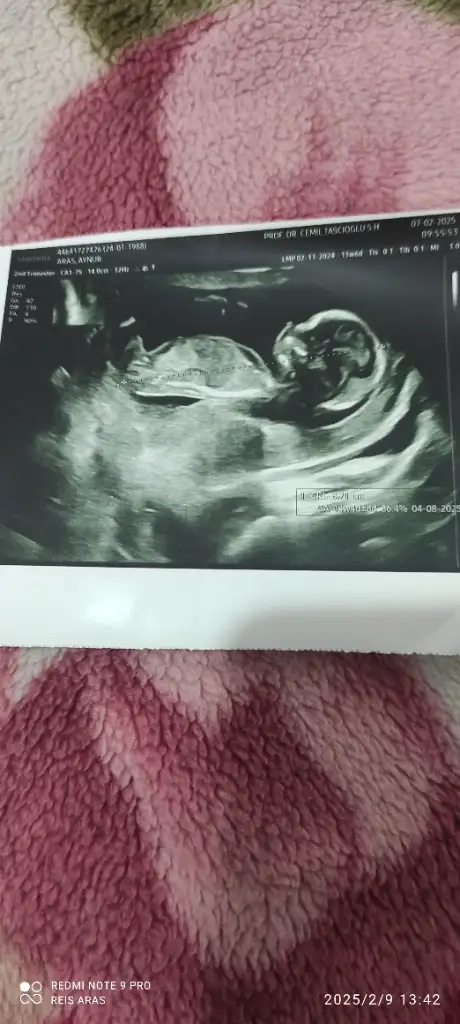

1.fotoğraf dün ki diğer 12. HaftalıkkenUltrason foto varsa yuklermısınız son gittiğiniz

TeşekkürlerKızınız olcak ramzi teorisine göre nubu karşıya bakıyor

Sizce benimki ne anlıyor musunuz cinsiyetten çok merak ediyorum.Kızınız olcak ramzi teorisine göre nubu karşıya bakıyor benım görüşüme göre